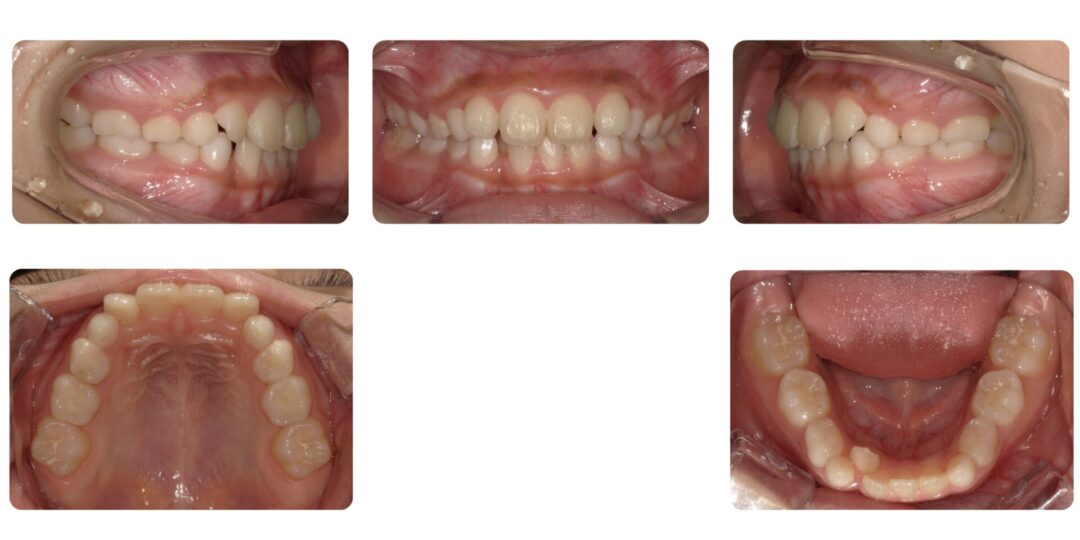

右下2番舌側転移を伴う叢生|初診時8歳

矯正治療前

矯正治療後

右下の2番目が後ろに下がっている

第一期治療 上下拡大床による歯列矯正

1年3ヶ月

自由診療 基本料金¥330,000 処置料¥3,300